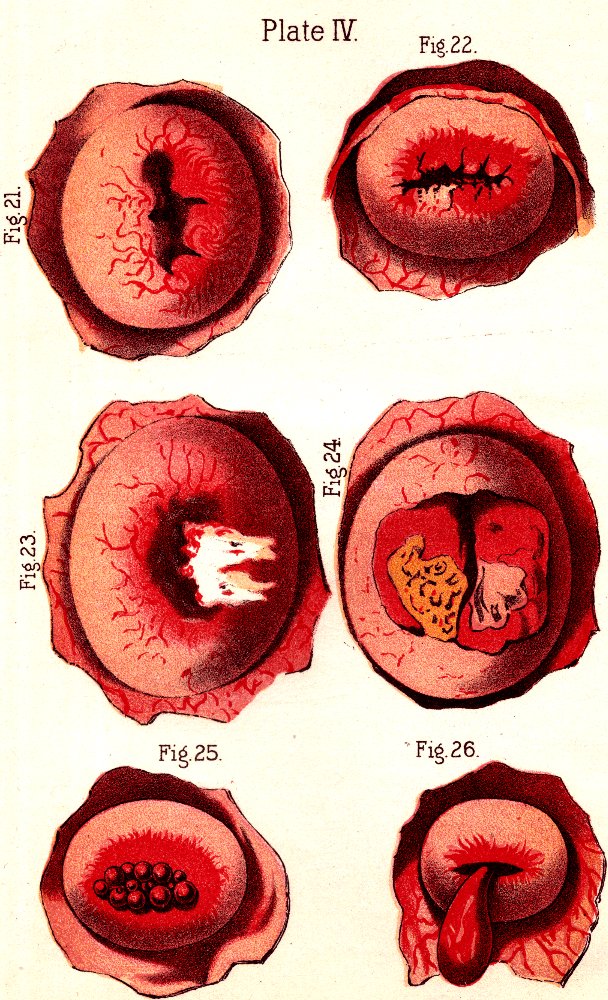

Fig. 3. THE UTERINE DILATOR. This instrument is introduced

into the canal of the uterine neck with its blades closed. By means of the

thumb-screw the blades are then separated as shown in this illustration,

the cervical canal being thereby dilated to the required extent.

Treatment. From the nature of this malady, it will readily be seen that no medical treatment can effect a radical cure. We must therefore resort to surgery. In a small proportion of cases, the stricture may be cured by repeated dilations of the constricted part of the cervical canal. This may be accomplished by using a very smooth probe which is fine at the point, but increases in size, so that its introduction will widen and expand the orifice and canal. The stricture may be overcome in many cases by using different sized probes. In some instances, we have employed the uterine dilator, represented by Fig. 3. We have also introduced sea-tangle and sponge tents into the neck of the womb, and allowed them to remain until they expanded by absorbing moisture from the surrounding tissues. The latter process is simple, and in many cases preferable. By means of a speculum (see Figs. 15 and 16), the mouth of the womb is brought into view, and the surgeon seizes a small tent with a pair of forceps and gently presses it into the neck of the womb, where it is left to expand and thus dilate the passage. If there seems to be a persistent disposition of the circular fibers of the cervix to contract, and thus close the canal, a surgical operation will be necessary to insure permanent relief. In performing this operation, we use a cutting instrument called the hysterotome (see Figs. 4 and 5). By the use of this instrument, the cervical canal is enlarged by an incision on either side. The operation is but slightly painful, and, in the hands of a competent surgeon, is perfectly safe. We have operated in a very large number of cases and have never known any alarming or dangerous symptoms to result. After the incision, a small roll of cotton, thoroughly saturated with glycerine, is applied to the incised parts, and a larger roll is introduced into the vagina. The second day after the operation, the cotton is removed, the edges of the wound separated by a uterine sound or probe, and a cotton tent introduced into the cervix, and allowed to remain, so that it will expand and thus open the wound to its full extent. This treatment must be thoroughly applied, and repeated every alternate day, until the incised parts are perfectly healed.